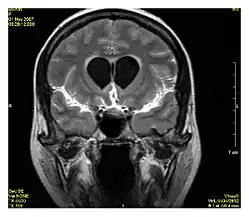

Cardiovascular

MR angiogram in congenital heart disease

Cardiac MRI is complementary to other imaging techniques, such as echocardiography, cardiac CT, and nuclear medicine. It can be used to assess the structure and the function of the heart.[42] Its applications include assessment of myocardial ischemia and viability, cardiomyopathies, myocarditis, iron overload, vascular diseases, and congenital heart disease.[43]